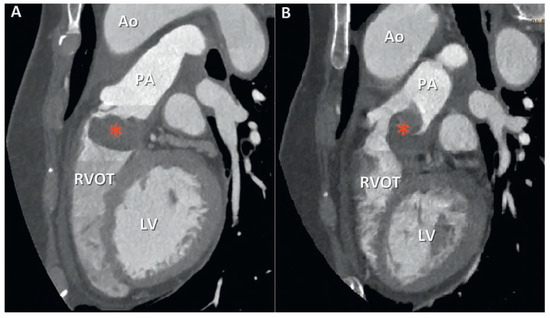

Pulmonary artery sarcomas are uncommon intracardiac tumours with poor prognosis. We report the case of a 69-year-old woman in good health presenting with rapidly progressive dyspnoea and an unfamiliar systolic murmur. Echocardiography revealed pulmonary valve stenosis due to an obstructing mobile mass. Imaging [...] Read more.

Pulmonary artery sarcomas are uncommon intracardiac tumours with poor prognosis. We report the case of a 69-year-old woman in good health presenting with rapidly progressive dyspnoea and an unfamiliar systolic murmur. Echocardiography revealed pulmonary valve stenosis due to an obstructing mobile mass. Imaging studies confirmed the presence of a contrast-enhancing lesion adherent to the valve, extending into the pulmonary trunk and right ventricular outflow tract, and suggestive of malignancy. Endovascular biopsy was attempted with no success. Surgical resection with autologous graft valve replacement and pulmonary artery reconstruction was performed. Postoperative histological examination confirmed the diagnosis of an undifferentiated pleomorphic sarcoma. Pulmonary artery sarcoma should be considered as a rare differential diagnosis in patients presenting with dyspnoea and a crescendo–decrescendo systolic murmur increasing with inspiration. Echocardiography is a useful first diagnostic approach but multi-imaging assessment is almost always necessary for definite diagnosis. Our case provides insights into the challenges met by cardiologists, radiologists and cardiac surgeons in the management of such cases. Full article

Show Figures

Figure 1